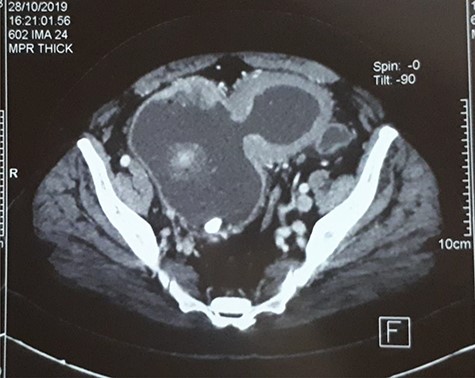

A 63-year-old man with a history of transurethral resection of prostate and a ballistic lithotripsy of bladder stone 15 years ago, presented with low urinary tract symptoms and hematuria. Cystoscopy showed multiple bladder stones and a bulky tumor mainly intradiverticular (Fig. 1). Partial resection of the tumor was done and pathology concluded on a squamous cell invasive bladder carcinoma. Since staging showed no metastatic lesion, a cystoprostatectomy was decided. Its execution was delayed because of a pulmonary embolism treated with curative anticoagulation and a severe paraneoplastic hypercalcemia treated with Zoledronic acid and veinous hydration on hospitalization. At Day 10 from admission and Day 60 after endoscopic resection of the tumor, the patient complained of abdominal pain, with diffuse tenderness and fever. Biology shows biologic inflammatory syndrome and kidney failure. Peritonitis was suspected and CT-scan showed a perforated bladder diverticulum with intraperitoneal effusion (Fig. 2). An emergency surgical investigation was executed, objecting a peritoneal cavity filled with nauseating hematic urine derived from a 2 cm disruption at the level of a posterolateral bladder diverticulum (Fig. 3). Radical cystectomy was performed. The patient was in severe septic shock requiring catecholamines and the procedure had to be shortened. No pelvic lymphadenectomy was done and bilateral ureterostomy was chosen as urinary diversion. The intervention lasted 2 h and there was no significant blood loss.

Emergency CT-scan showing intraperitoneal swallowing (blue arrows) due to a fistulization of the bladder (green arrow).